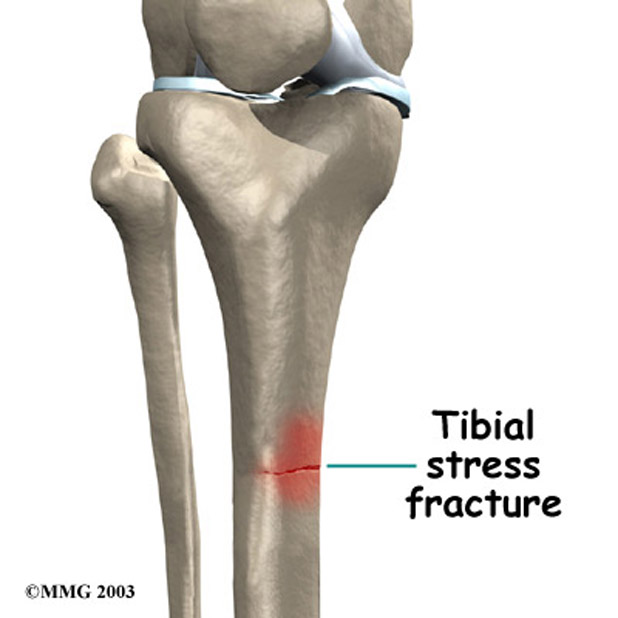

A stress fracture injury

A serious stress fracture injury